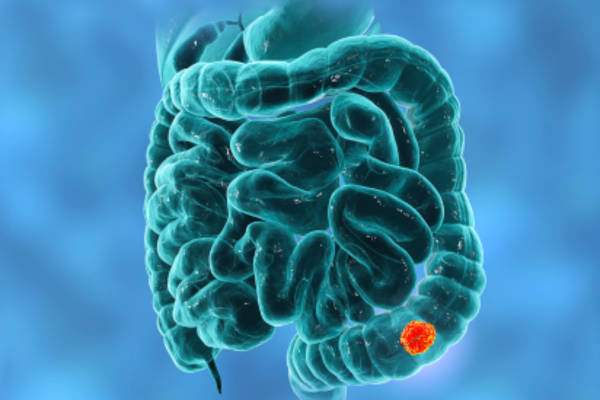

Upper and lower gastrointestinal bleeding can be life-threatening, presenting with vomiting blood, black stools, or severe weakness. It commonly occurs due to ulcers, tumors, or abnormal blood vessels.

Embolisation precisely blocks the bleeding vessel using catheters, controls bleeding rapidly, avoids emergency surgery, and stabilizes patients safely.